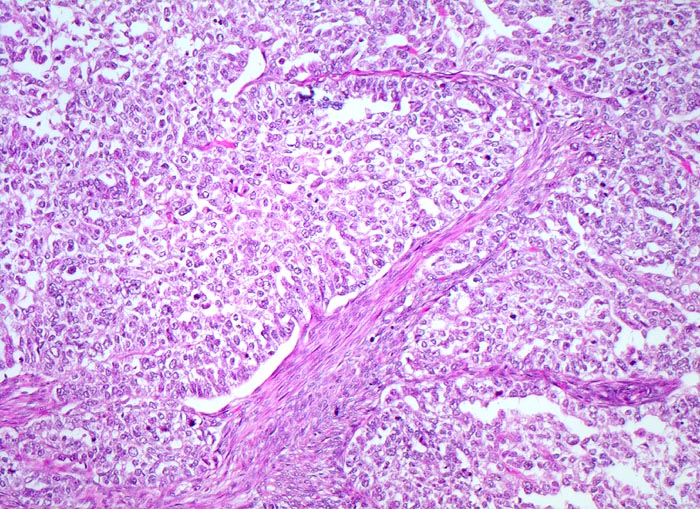

PathoPic – image database / PathoPic ID 4442 - wenig differenziertes endometrioides Adenokarzinom

wenig differenziertes endometrioides Adenokarzinom

Vorwiegend solide zellreiche invasive Karzinomanteile. Zwischen den soliden Tumorzellplatten schmale Streifen von glatter Muskulatur des Myometriums.

Exophytischer, in das Uteruscavum hineinragender, weicher fokal hämorrhagischer Tumor ausgehend von der Uterushinterwand. Das Tumorgewebe infiltriert die innere Hälfte des Endometriums.

Postmenopausale Blutung. Diagnose eines endometrioiden Adenokarzinoms in der Corpuskurettage. Daraufhin Hysterektomie, Adnexektomie und Lymphadenektomie.

Die Gradierung der endometrioiden Adenokarzinome (G1 bis G3) basiert auf dem Anteil solider Tumoranteile verglichen mit dem Anteil glandulärer Tumoranteile. Wenig differenzierte Tumoren bestehen zu über 50% aus soliden Tumorarealen. Schwere Zellatypien in einem architektonisch hochdifferenzierten Tumor mit hohem glandulärem Anteil erhöhen den Tumorgrad. Wenig differenzierte Tumoren haben eine schlechtere Prognose.